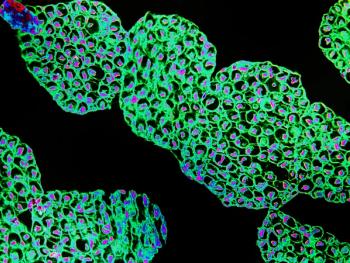

Several new studies feature developments in remyelination in MS. Oligodendrocyte precursor cells may be a promising target for MS treatments, and microRNA expression are perhaps an attractive MS biomarker.